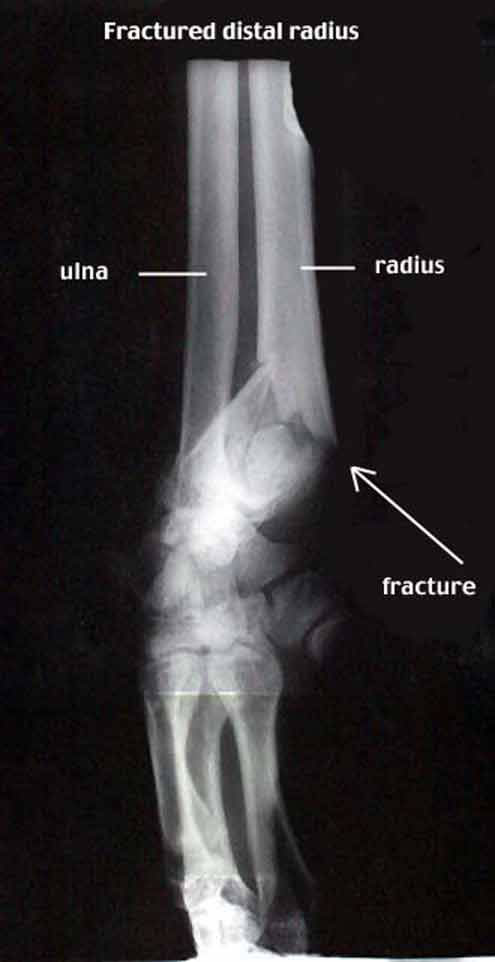

FG/distal2.jpg